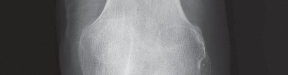

2. التصوير بالأشعة السينية (X-ray):

تُعد الأشعة السينية هي الأداة التشخيصية الأساسية لتقييم خشونة الركبة. يلتقط الأستاذ الدكتور هطيف صورًا للركبة من زوايا مختلفة، بما في ذلك صور الوقوف (Weight-bearing X-rays)، والتي تُظهر المفصل تحت تأثير وزن الجسم الطبيعي. تُظهر الأشعة السينية ما يلي:

- تضييق المسافة المفصلية: خاصة في الجانب الإنسي للركبة، مما يشير إلى تآكل الغضروف.

- تكون النتوءات العظمية (Osteophytes): وهي نتوءات عظمية صغيرة تتشكل حول حواف المفصل نتيجة للتآكل.

- تغيرات في كثافة العظام: مثل التصلب تحت الغضروفي (Subchondral Sclerosis).

- درجة الانحراف التقوسي: قياس الزوايا المحورية للساق لتحديد مدى التقوس بدقة.